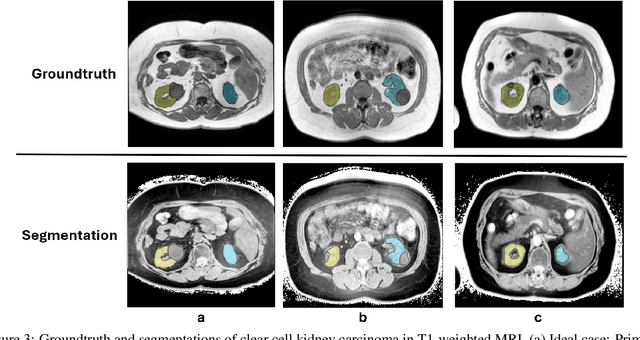

Abstract:Kidney abnormality segmentation has important potential to enhance the clinical workflow, especially in settings requiring quantitative assessments. Kidney volume could serve as an important biomarker for renal diseases, with changes in volume correlating directly with kidney function. Currently, clinical practice often relies on subjective visual assessment for evaluating kidney size and abnormalities, including tumors and cysts, which are typically staged based on diameter, volume, and anatomical location. To support a more objective and reproducible approach, this research aims to develop a robust, thoroughly validated kidney abnormality segmentation algorithm, made publicly available for clinical and research use. We employ publicly available training datasets and leverage the state-of-the-art medical image segmentation framework nnU-Net. Validation is conducted using both proprietary and public test datasets, with segmentation performance quantified by Dice coefficient and the 95th percentile Hausdorff distance. Furthermore, we analyze robustness across subgroups based on patient sex, age, CT contrast phases, and tumor histologic subtypes. Our findings demonstrate that our segmentation algorithm, trained exclusively on publicly available data, generalizes effectively to external test sets and outperforms existing state-of-the-art models across all tested datasets. Subgroup analyses reveal consistent high performance, indicating strong robustness and reliability. The developed algorithm and associated code are publicly accessible at https://github.com/DIAGNijmegen/oncology-kidney-abnormality-segmentation.